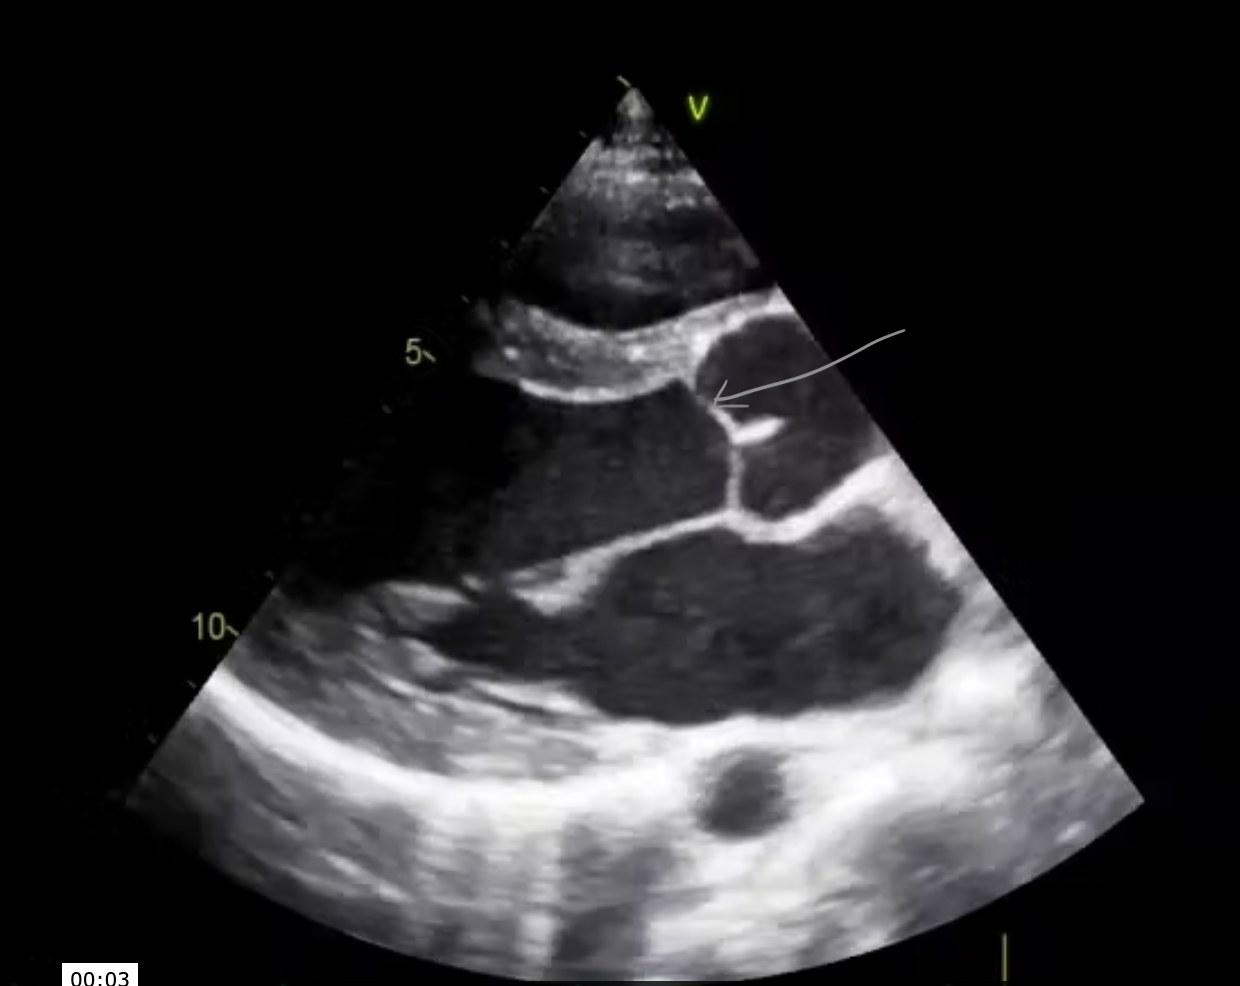

Q

In this PLAX view, the arrow is pointing to the:

A

RCC

*Registered Nurse

The arrow (gray one) in this image is pointing to the:

Left main coronary artery

*the image demonstrates the left coronary artery originating from the left coronary cusp